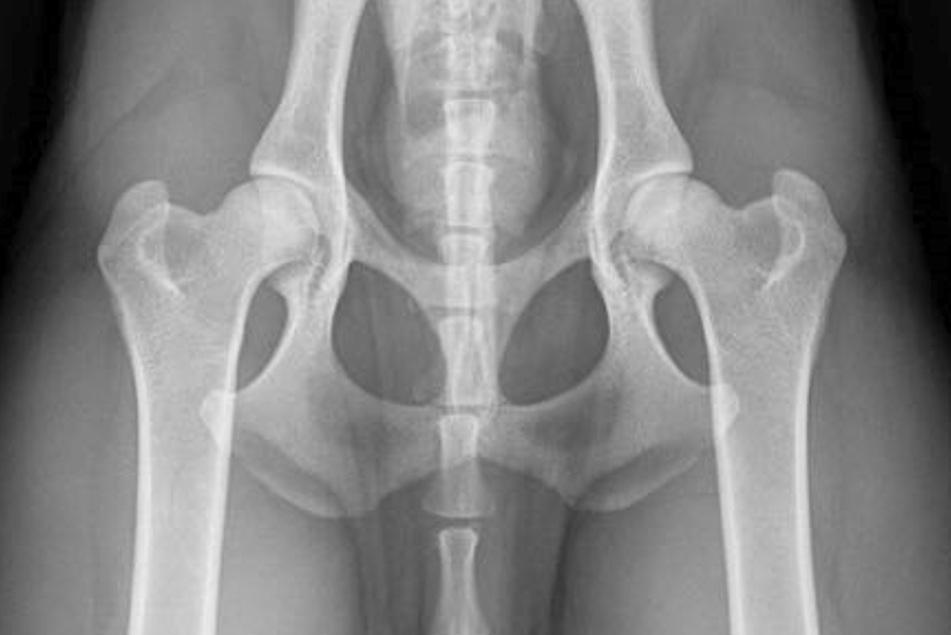

Hälsa HD Höftledsdysplasi är en felaktig utveckling av höftleden LTV Övergångskota – Lumbosacral Transitional Vertebrae (LTV) - är en missbildning i ryggslutet Katarakt Grå Starr inom Bretonrasen i Sverige Hälsa-allmänt Hälsobeskrivning generellt i rasenoch förekomst av hälsoproblem Avelsstrategi RAS - Rasspecifik Avelsstrategi Uppfödare Hitta Uppfödare som tillhör Bretonklubben Aktuella kullar Här hittar du planerade och födda valpkullar inom Bretonklubben Hanhundslista Lista på alla svenska meriterade Breton-hanhundar